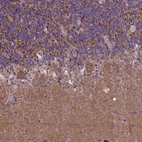

Immunohistochemical staining of human cerebellum shows moderate cytoplasmic positivity in Purkinje cells and cells in granular layer.